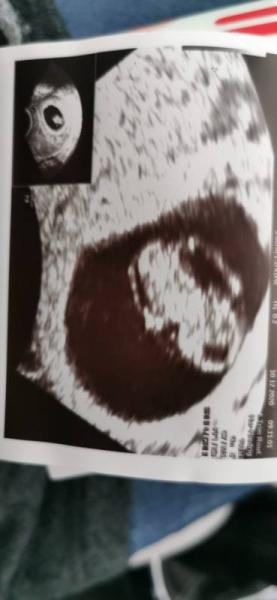

Heute war ich nun das zweite Mal beim FA. Es ist alles supi. Das kleine ist nun 14mm. Das schlägt kräftig der nächste termin ist dann am 7.1. Jetzt heißt es wieder geduldig warten. Ich hoffe euch geht's auch allen gut?

Bild zu 2.Termin< 3 - Forum für Juli - Mamis